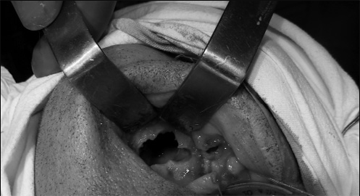

Решено произвести операцию, под общим обезболиванием: резекция области ОН верхней челюсти, ревизия верхнечелюстной пазухи справа. После обнажения кости верхней челюсти, была обнаружена четкая граница остеонекроза (рис.3). Произведена остеотомия некротизированного участка в пределах здоровых тканей (рис.4). После удаления некроти- зированного участка кости, открылось широкое сообщение с верхнечелюстной пазухой, в которой об-наружились полипозные разрастания и гной (рис.5). Были удалены патологически измененные ткани из верхнечелюстной пазухи, образовали сообщение с нижним носовым ходом, произвели тампонаду верхнечелюстной пазухи, вывели конец тампона через соустье, образованное с нижним носовым ходом. В конце, рана в полости рта была ушита наглухо (рис.6). Одновременно больному назначили антибиотики широкого спектра действия (отменили через 5 дней после операции) и местные антисептики.

Рис.4. Остеотомия некротизированного участка альвеолярного отростка в пределах здоровых тканей |